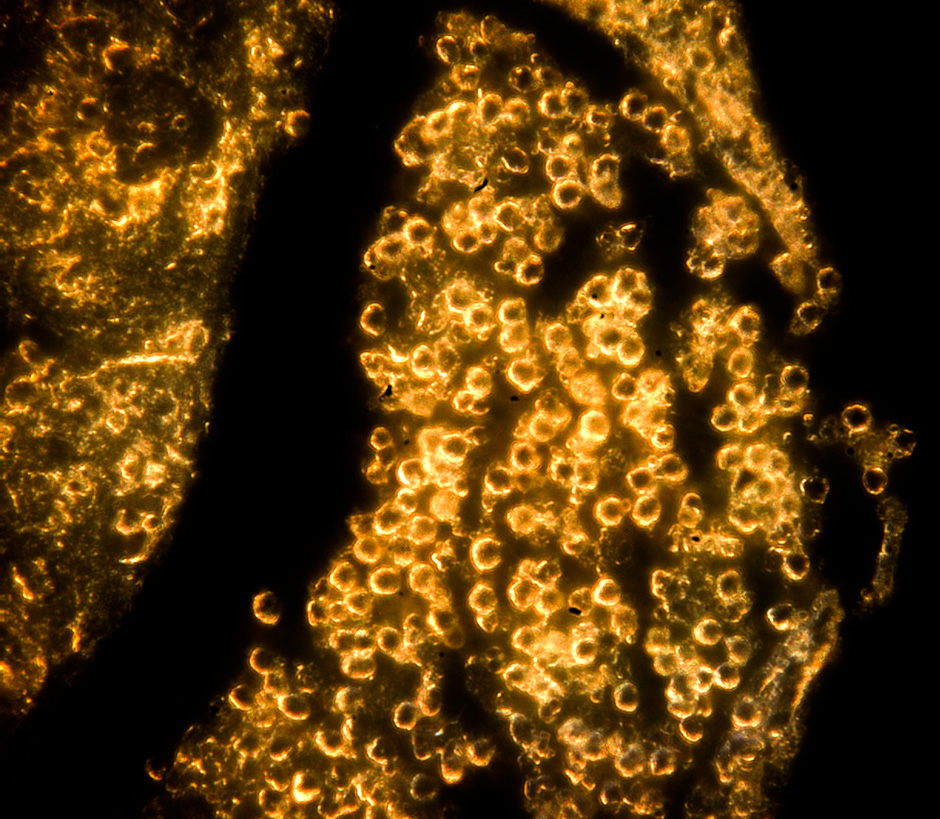

In the work, the authors were also able to show that gold nanoparticles accumulate in the cytoplasm of cells, both tumor glioma and immune cells — macrophages. This opens up the possibility of individual diagnosis and therapy of tumors. In the future, it is planned to modify the surface of nanoparticles with special molecules to find a tumor in the body. However, researchers offer another option for using their method — as a bioconstructor.